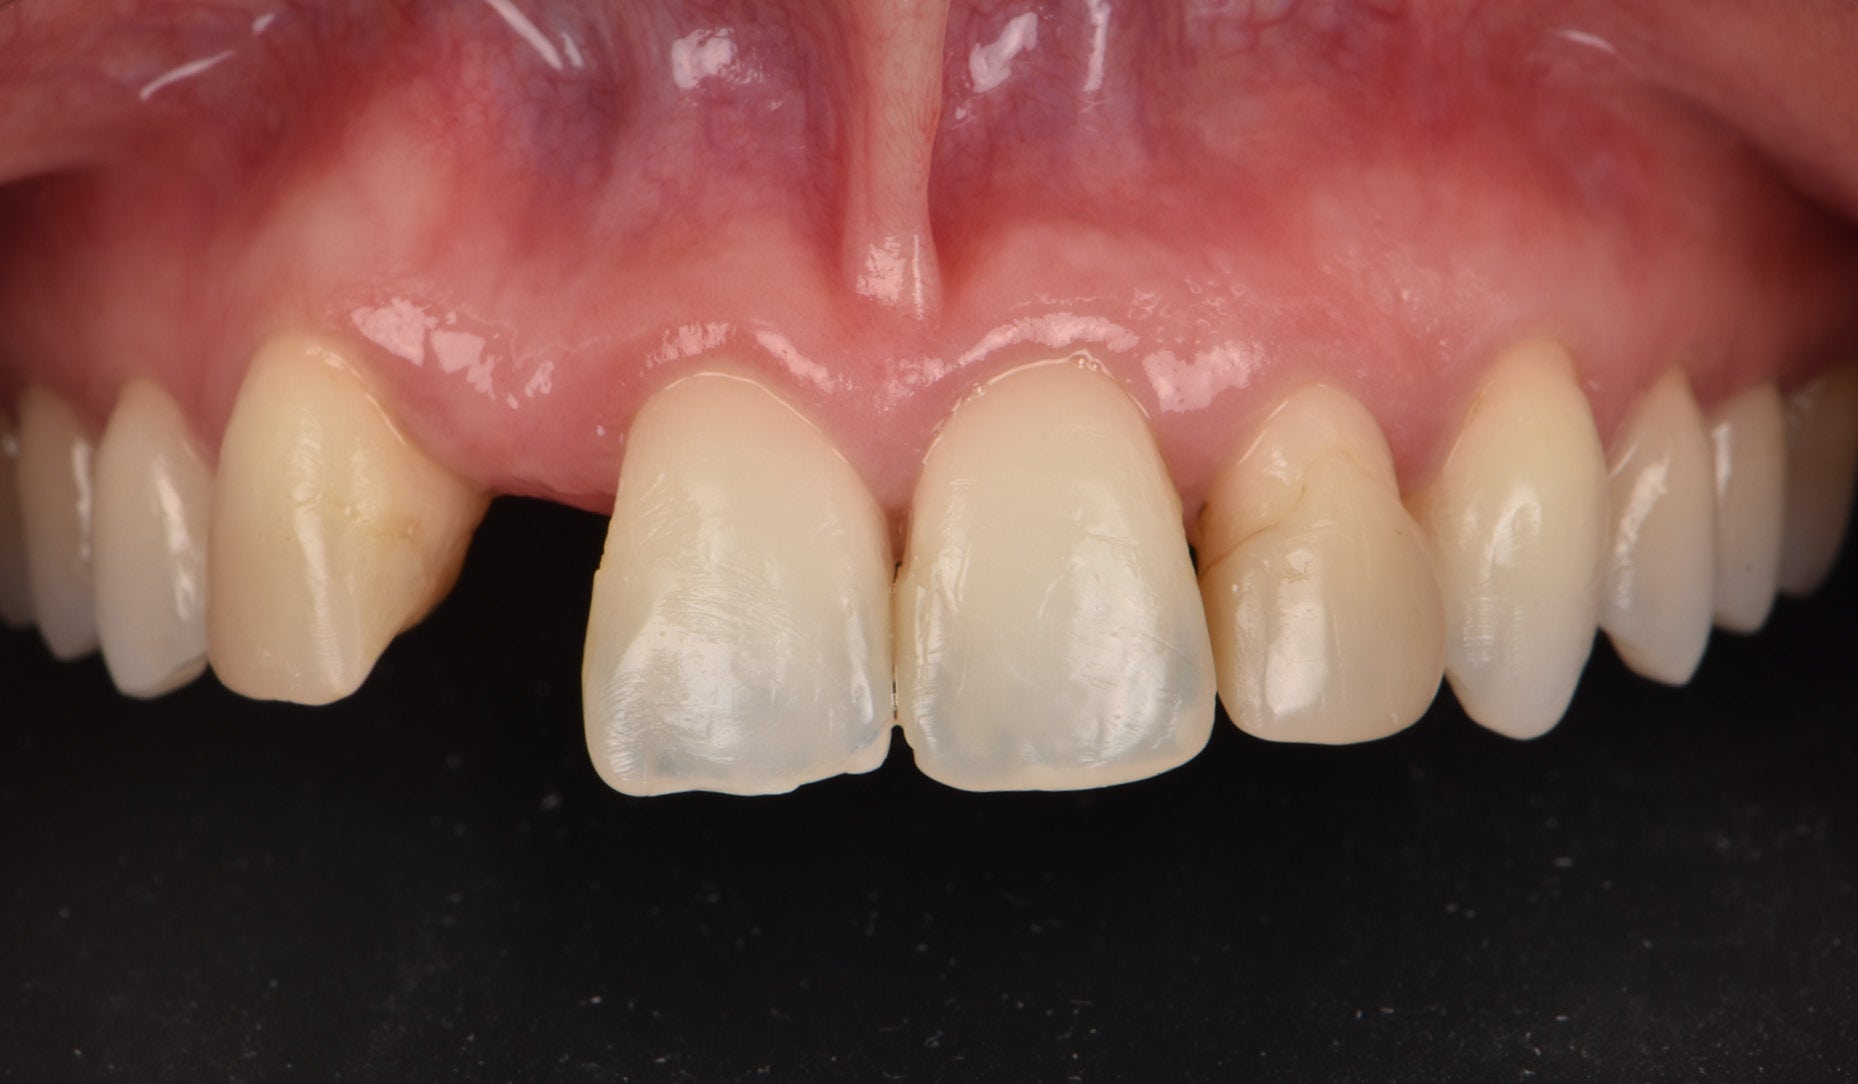

Clinical Cases, Labside Two high-strength ceramics, one micro-layering system Case by DT Andreas Chatzimpatzakis AESTHETIC AND EFFICIENT SMILE MAKEOVER Most patients asking for a smile makeover desire custom solutions rather than an off-the-peg smile: Individual tooth shapes that fit their face and their character, an internal play of colours that matches their age and natural dentition. Modern dental materials allow us to deliver what they demand in many situations – usually at a reasonable price. For a long time, however, we have been facing challenges when combining cosmetic and medically indicated treatment – e.g. a smile makeover including the rehabilitation of a missing lateral incisor. A straightforward solution – using lithium disilicate veneers alongside a zirconia cantilever bridge, both finished with their respective porcelain systems – would have been complicated by potential differences in the final appearance. With CERABIEN™ MiLai (Kuraray Noritake Dental Inc.), a set of internal stains and porcelains designed for micro-layering, the situation is different: Suitable for micro-layering on zirconia and lithium disilicate, it supports its user ideally in creating a harmonious smile even when the two framework materials are combined. A NEW CUSTOM SMILE The following patient case is a perfect example: A female patient with a missing lateral incisor, multiple visible composite restorations in the anterior region and an enamel fracture at her incisal edge desired a smile makeover. The selected materials were Amber Press LT (HASS), shade A1, for four veneers on the central incisors and the left lateral incisor and canine (teeth # 11, 21, 22 and 23 according to the FDI notation) and KATANA™ Zirconia YML (Kuraray Noritake Dental Inc.), shade A2, for the planned cantilever bridge on the maxillary right canine, replacing the missing lateral incisor (teeth # 12 and 13). Fig. 1. Female patient with a missing maxillary lateral incisor and multiple composite restorations in the anterior area – a smile makeover is desired. Fig. 2. Patient with mock-up. Fig. 3. Minimally invasive preparation through the mock-up, which takes into account the minimum space required for the planned materials and restorations. Fig. 4. Teeth prepared for the all-ceramic restorations. Fig. 5. Occlusal view of the maxillary teeth after tooth preparation. Fig. 6. Full-contour veneers and cantilever bridge on the model. Fig. 7. Restorations after a cutback limited to the vestibular and incisal area. Fig. 8. CERABIEN™ MiLai LT1 is applied to the middle and cervical area of the zirconia cantilever bridge. Fig. 9. CERABIEN™ MiLai Value Liner 2... Fig. 10. … and Value Liner 1 applied to the incisal area of the central and lateral incisor restorations. Fig. 11. CERABIEN™ MiLai porcelain Creamy Enamel mixed with Value Liner 2 (70/30) added to the middle and cervical areas of the four lithium disilicate restorations to increase and control the value. Fig. 12. ... while E2 is added to the incisal area of both canines. Fig. 13. Restorations covered by a layer of Tx ... Fig. 14. ... and LTx. Fig. 15. Appearance of the restorations after the first bake. Fig. 16. Adding translucency and opalescence to the cervical area with LT1 and brightness to the ridges with Creamy Enamel. Fig. 17. Completion of the enamel surface with a cover layer of LTx, which is responsible for a high translucency and opalescence. Fig. 18. Result of the second bake. Fig. 19. Final restorations with a natural self-glaze effect on the model. Fig. 20. Final restorations with a natural self-glaze effect in the patient’s mouth. Fig. 21. Smooth optical integration of the restorations. Fig. 22. Beautiful treatment outcome. CONCLUSION With the described approach and selected materials, it was possible to create restorations with a natural shade, shape and texture. They matched not only the appearance of the remaining natural teeth, but also showed internal consistency across the selected framework materials. The technical procedure was quite straightforward and efficient, while the result speaks for itself. Special thanks to Dr. Kanellos Ioannis for the collaboration on this case and for kindly providing the pre- and post-treatment photographs that complemented it. Dental technician: ANDREAS CHATZIMPATZAKIS Based in Athens, Greece, Andreas Chatzimpatzakis is the founder and director of ACH Dental Laboratory (since 2000), specializing in refractory veneers, lithium disilicate, zirconia, and implant prostheses. He graduated in Dental Technology from the University of West Attica and received advanced training in all-ceramic restorations in Helsinki and Japan under renowned masters including Shigeo Kataoka. Since 2017, he has served as an international trainer for Kuraray–Noritake Dental Inc., delivering lectures and hands-on courses worldwide on advanced ceramic techniques. He has also held roles as Key Opinion Leader for MPF Brush Co., Ambassador for Hass Co., and Editor-in-Chief of Laborama. An active member of the Hellenic Academy of Aesthetic Dentistry, his work and articles have been published in both Greek and international journals. Jan 21, 2026 Dental Technician Kuraray Noritake Prosthodontics Clinical Case Katana Zirconia YML CERABIEN MiLai Prosthetic dentistry Lab Dental Ceramics Cad Cam Discs KATANA Zirconia YML View Product CERABIEN MiLai View Product Subscribe to our Newsletter Join thousands of dental professionals and receive free advice that can help you and your career. We will not spam or share your e-mail.